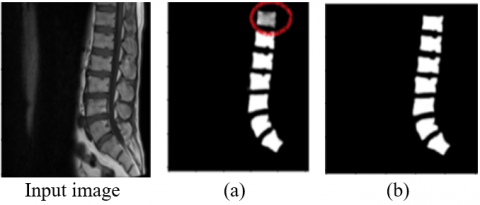

We noticed in Figure 16 that there was overfitting in the results, which led to the loss of some information, which appeared in the form of a missing part in the spine segmentation image, as shown by the circle in Figure 16(a), in contrast to the results of u_net, where the results were good and appear This is due to the accuracy of the segmentation of the spinal vertebrae, which appeared clearly as shown in Figure 16(b).

Figure 16. (a) prediction with 30% test and 70% training, (b) prediction resulting with 20% test and 80% training